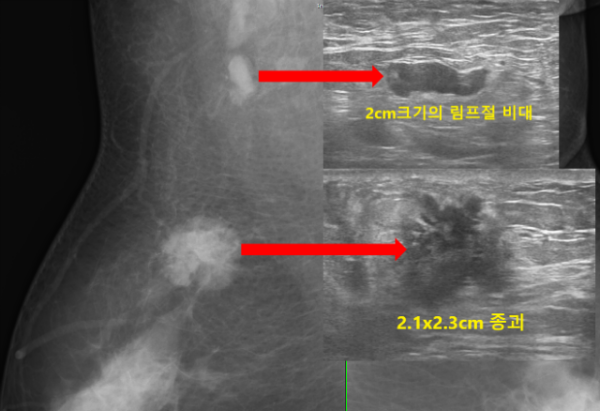

초음파상 오른쪽 유방의 9시방향에 가로x세로의 길이가 약 2.1x2.3cm 크기의 불규칙한 모양과 경계를 보이는 유방암이 의심되는 결절이 관찰되었습니다.

또한 오른쪽 겨드랑이에도 유방암의 전이가 의심되는 2cm 크기의 커진 림프절이 관찰되었습니다.